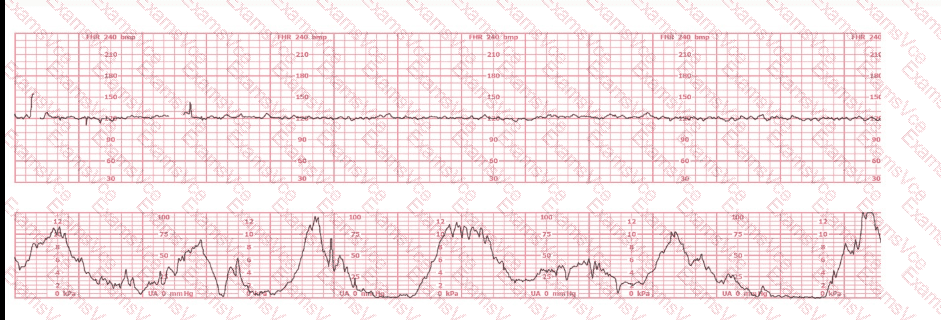

The tracing demonstrates an FHR baseline around 145–150 bpm, which falls within the normal range of 110–160 bpm. NCC references define baseline as the mean FHR rounded to increments of 5 bpm over a 10-minute window.

The strip shows minimal variability, with amplitude fluctuations approximately 0–2 bpm.

This tracing shows minimal variability, not moderate, so it cannot be Category I.

No accelerations are present. Lack of accelerations alone does not classify the tracing as Category III.

There are no recurrent late decelerations, no recurrent variable decelerations, and no prolonged decelerations. Without these, and with minimal variability, the tracing does not meet Category III criteria.

Because this tracing shows minimal variability, a normal baseline, no accelerations, and no recurrent decelerations, it fits squarely into Category II.

Therefore, the correct classification is Category II.